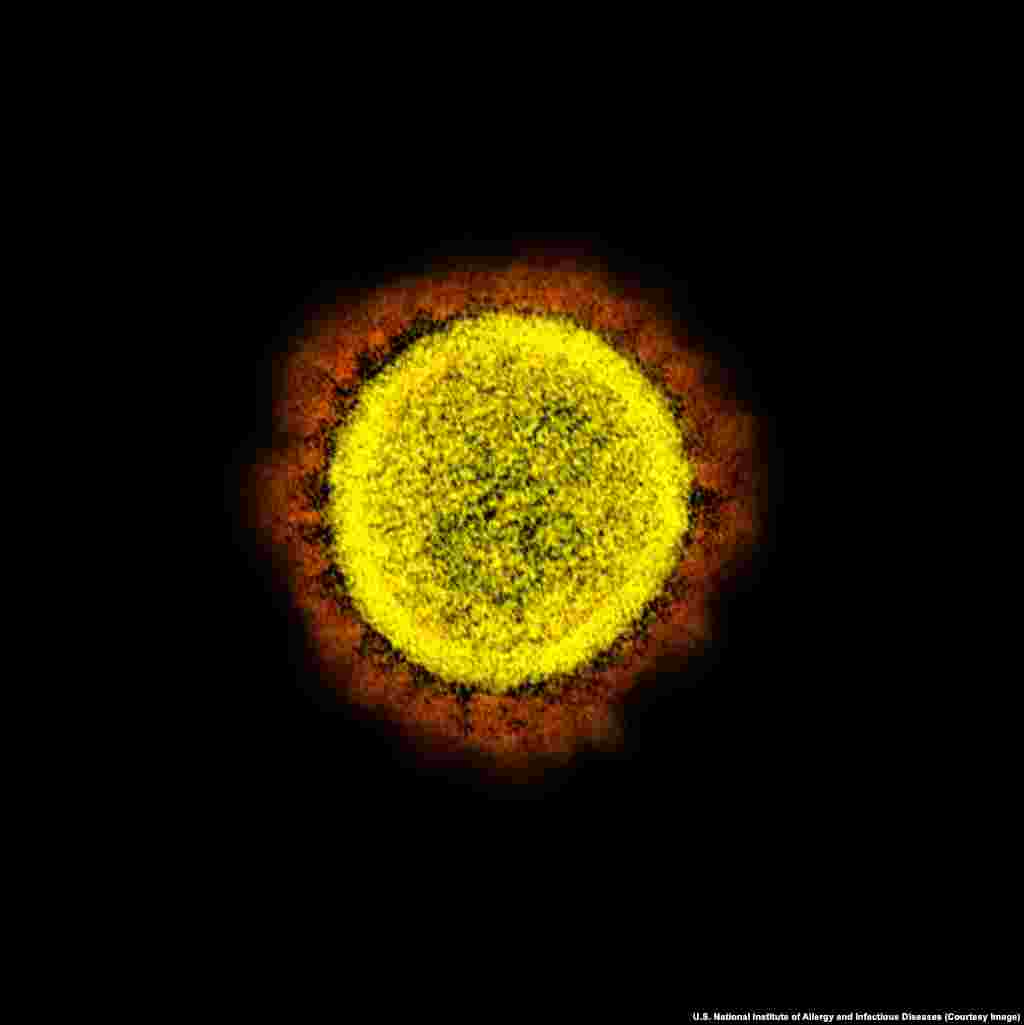

4

Вирион SARS-CoV-2.

Под микроскопом вокруг вируса видны отростки, напоминающие солнечную корону, поэтому в его названии присутствует слово "корона". В переводе с латинского "корона" означает ореол или венец.

Под микроскопом вокруг вируса видны отростки, напоминающие солнечную корону, поэтому в его названии присутствует слово "корона". В переводе с латинского "корона" означает ореол или венец.